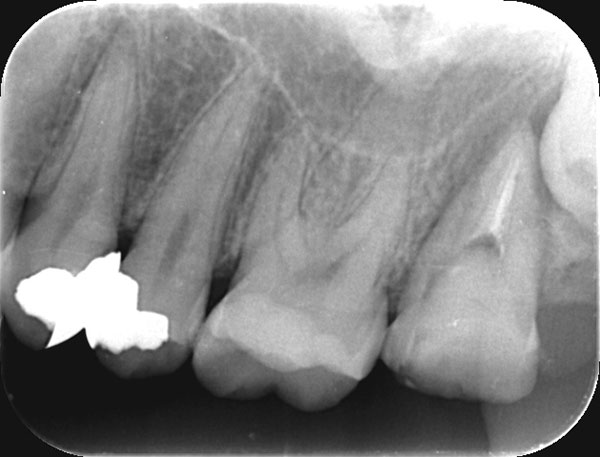

術前

術後

症例について

主訴:

最近冷たい物がよく染みる

治療内容:

炎症を起こした歯髄を部分的に除去し、神経をできるだけ残すことを目的とした治療です。

治療期間:90分 1回

費用:33,000円(税込)

治療に関わるリスクまたは副作用:

経過中に症状が出た場合、根管治療が必要になることがあります。